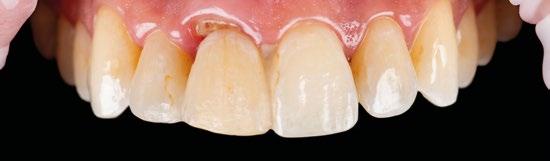

Empezaremos por un protocolo de fotografía intraoral que nos permita ver la situación inicial del paciente y que a su vez nos sirva de prueba legal ante cualquier tipo de reclamación. (Figuras 1 a 3)

Por otro lado, es imprescindible y fundamental realizar un CBCT de la arcada a tratar para poder visualizar los tejidos duros y hacer una primera valoración del lecho implantario y de la patología existente. (Figura 4)